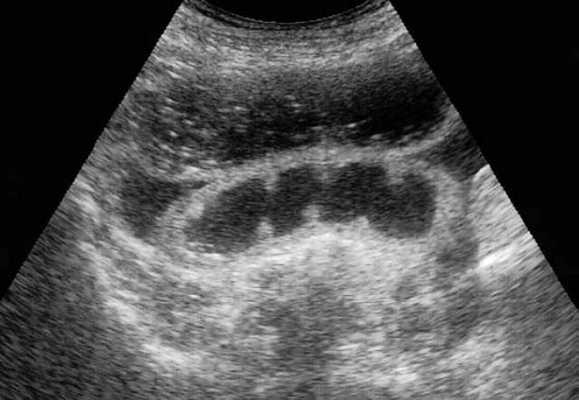

Мальротация кишечника (нонротация) у мужчины 39 лет.

(а, б) Тощая кишка — прямое продолжение двенадцатиперстной (стрелка, а), отсутствуют нормальные 3-й и 4-й сегменты двенадцатиперстной кишки, а также двенадцатиперстно-тощекишечный переход (звездочка, б).

(в, г) Петли тонкой кишки (прямые стрелки) лежат в левой половине брюшной полости, а ободочная кишка (изогнутые стрелки) — в правой половине. Заворот средней кишки у мальчика 11 лет.

Врожденная мальротация кишечника обусловлена нарушением нормальной ротации первичной кишки в направлении против часовой стрелки. Среди широкого разнообразия вариантов мальротации в клинической практике наиболее часто встречают полное отсутствие ротации (нонротация). При этом состоянии тощая кишка служит прямым продолжением двенадцатиперстной, при этом отсутствуют 3-й и 4-й сегменты двенадцатиперстной кишки и двенадцатиперстно-тощекишечный переход. Петли тонкой кишки лежат в левой половине брюшной полости, а ободочная кишка — в правой половине. При завороте средней кишки ножка брыжейки сужена, а двенадцатиперстно-тощекишечный переход (местонахождение связки Трейтца) чаще расположен низко, по правую сторону от средней линии. Такие условия приводят к перекручиванию неправильно фиксированной тонкой кишки, а верхние брыжеечные артерия и вена располагаются в короткой и суженной ножке брыжейки.